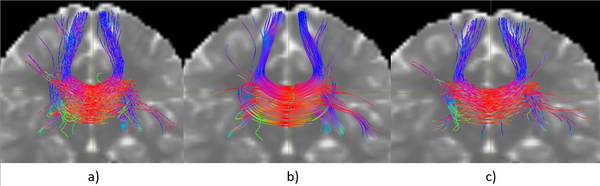

La Figura 1 muestra una comparación visual de tres tractografías generadas a partir de una misma semilla localizada en el cuerpo calloso, utilizando diferentes algoritmos. Todas las tractografías fueron generadas con la misma cantidad de streamlines, lo que permite una observación cualitativa más equitativa entre métodos.

A partir de esta visualización inicial, se pueden identificar algunas diferencias notables entre las tres reconstrucciones. Si bien no es posible realizar conclusiones definitivas sin un respaldo cuantitativo, esta inspección cualitativa sugiere ciertos aspectos a destacar:

Es importante señalar que estos resultados corresponden únicamente a una inspección visual preliminar. Si bien el comportamiento del algoritmo propuesto resulta alentador, será necesario complementar este análisis con métricas cuantitativas en las siguientes secciones para validar su desempeño de forma objetiva.

| Figura 1: Comparación visual de tractografías generadas desde una semilla en el cuerpo calloso: a) iFOD2, b) SD-Stream, c) Algoritmo propuesto. |